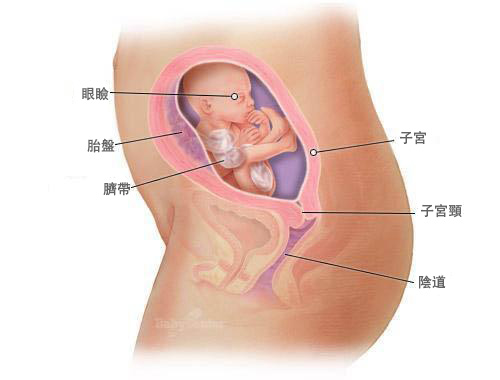

懷孕25周的胎兒是什麼樣子 附 胎兒每周發育標準參考表 壹讀

懷孕25周胎寶寶是怎麼樣的呢 孕婦要注意什麼呢 看完很喜人 壹讀

懷孕期第25週 寶寶階段發展 Superbaby

懷孕第25週 Mamaway媽媽餵懷孕哺乳育兒百科

孕25周 胎宝宝大脑飞速发育

懷孕25周的胎兒是什麼樣子 附 胎兒每周發育標準參考表 壹讀

懷孕25周胎寶寶是怎麼樣的呢 孕婦要注意什麼呢 看完很喜人 壹讀

懷孕25周的胎兒是什麼樣子 附 胎兒每周發育標準參考表 每日頭條